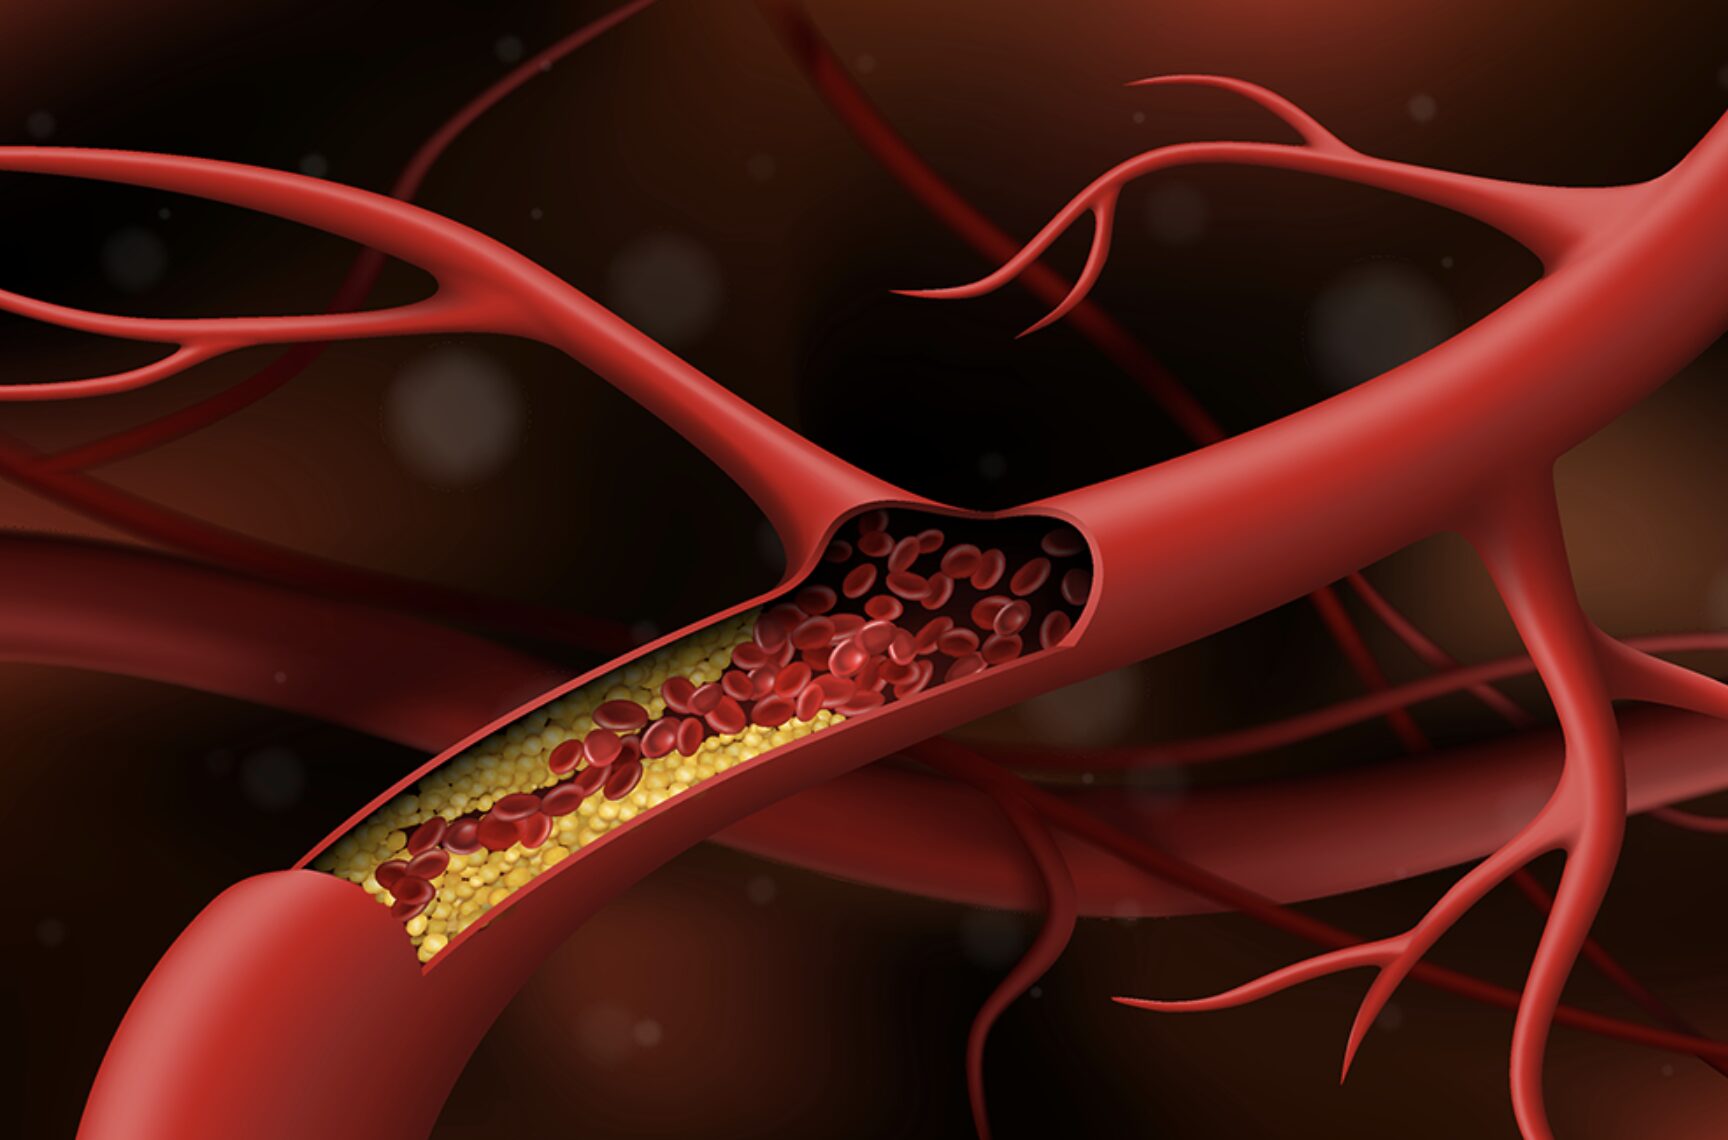

Tăng huyết áp mạn tính: Nguyên nhân và cách điều trị

Tăng huyết áp mạn tính là tình trạng huyết áp tăng cao trong thời gian dài. Huyết áp là áp lực mà máu đặt lên động mạch khi nó lưu thông trong cơ thể. Tim của bạn phải làm việc chống lại áp lực này để bơm máu. Đọc tiếp để tìm hiểu thêm về tăng huyết áp mạn tính và nguyên nhân, chẩn đoán, hay những ảnh hưởng tiêu cực tiềm ẩn đến cơ thể.

Kháng insulin làm tăng nguy cơ đột quỵ, đau tim thế nào?

Một trong những nguyên nhân gây đái tháo đường và nhiều rối loạn liên quan như: béo phì, rối loạn dung nạp glucose, rối loạn lipid máu và tăng huyết áp là tình trạng kháng Insulin.